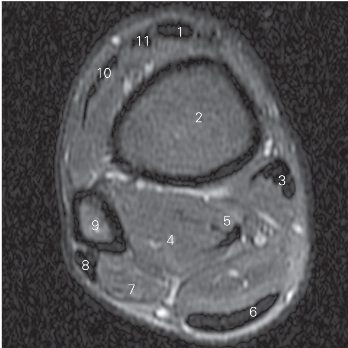

图5-35 经胫骨下段的横断层MR T2WI FS

1 胫骨前肌 tibialis anterior 2 胫骨 tibia

3 胫骨后肌 tibialis posterior 4

长屈肌 flexor hallucis longus

5 趾长屈肌 flexor digitorum longus 6 跟腱 tendo calcaneus

7 腓骨短肌 peroneus brevis 8 腓骨长肌 peroneus longus

9 腓骨 fibula

10 趾长伸肌 extensor digitorum longus

11

长伸肌 extensor hallucis longus